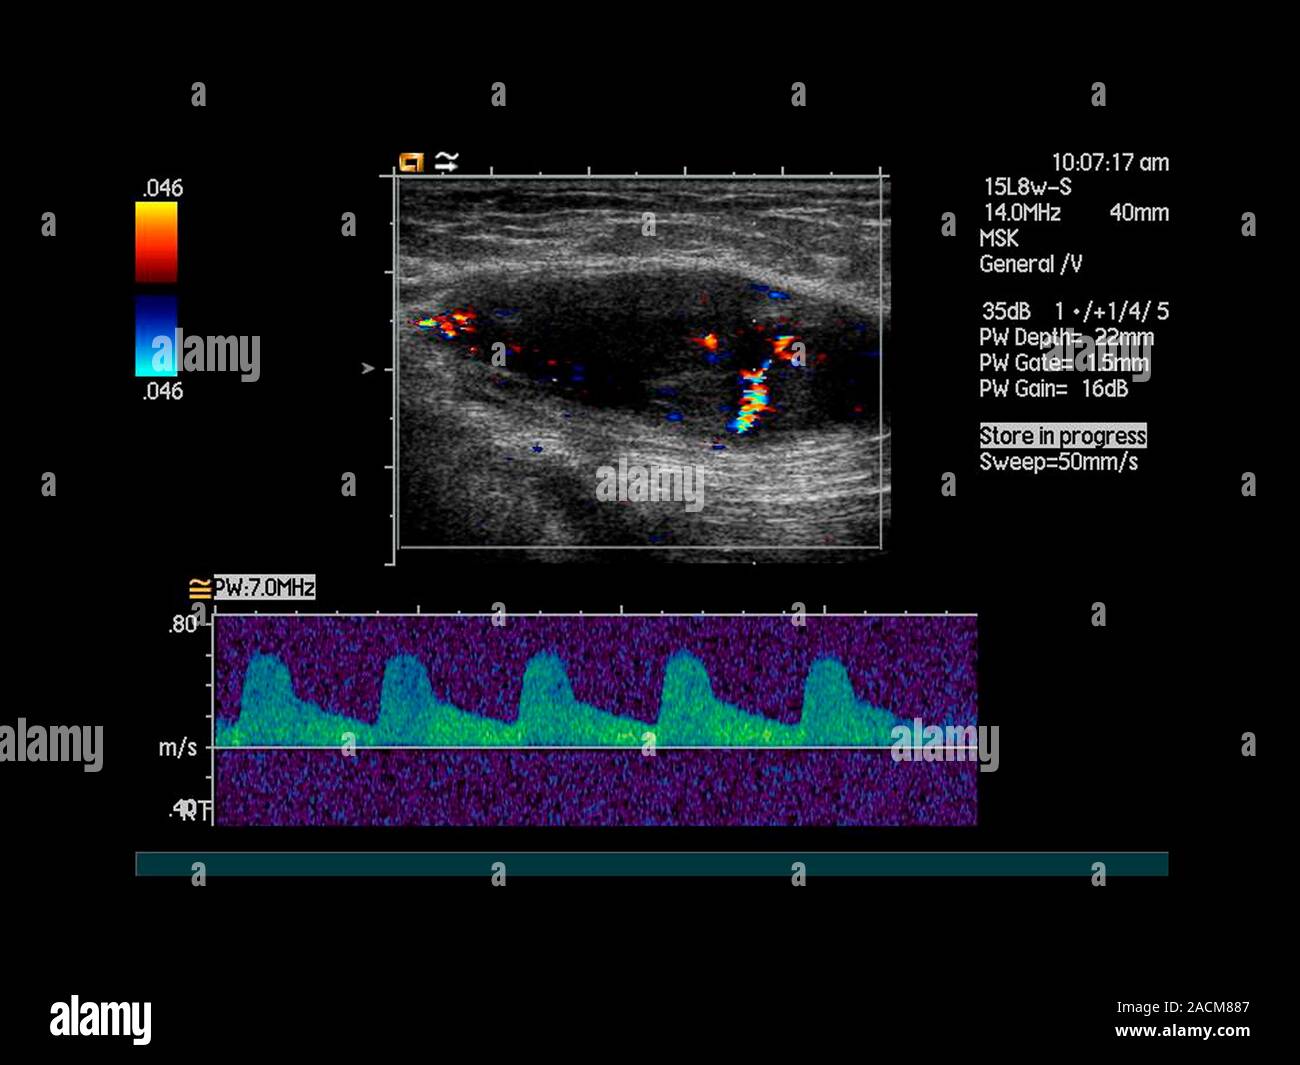

Buttock cancer. Doppler ultrasound scan of the buttock of a 45 year old woman showing increased Pain In Right Buttock Cheek Cancer As the cancer grows, it may cause: It’s a type of head and neck cancer. different causes of buttock pain can produce varied symptoms, including shooting, burning, numbness, tingling, or aching sensations. The vast majority of soft tissue sarcomas do not cause pain, which, unfortunately, leads people to mistakenly think they don't need an evaluation. a soft tissue. Pain In Right Buttock Cheek Cancer.